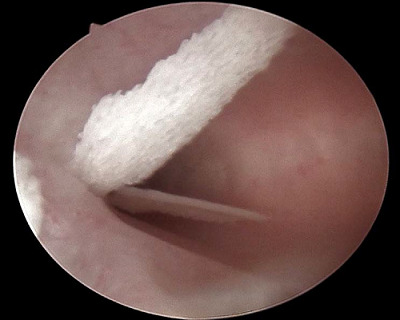

Case presentation: We present two cases of OM presented to the infertility clinic and discuss their similarities and discrepancies in presentation and risk factors. A transvaginal ultrasound raises suspicion about the diagnosis of OM with a hyperechoic mass and post-acoustic shadowing. An office hysteroscopy showed white, mesh-like bony sheets. Both cases underwent operative hysteroscopy to address surgical challenges, and the two cases were followed postoperatively for one year.